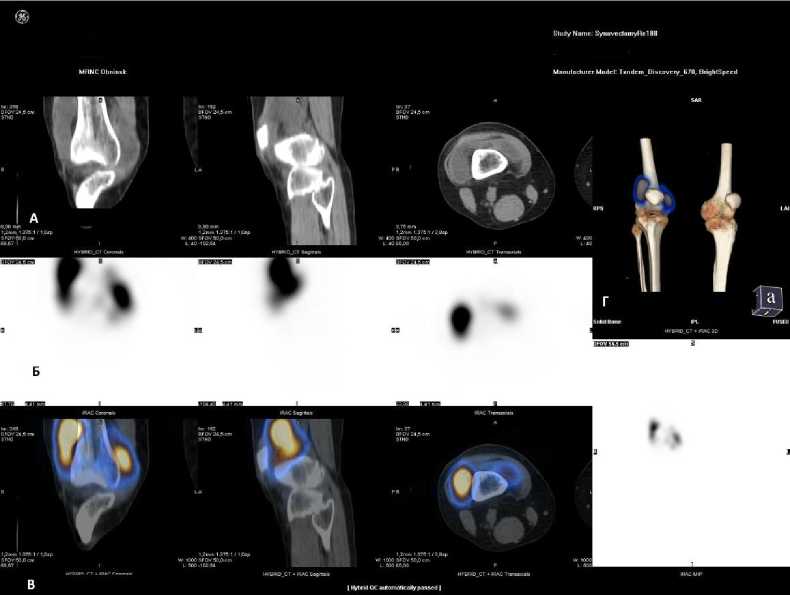

На рис. 4 показаны изображения ОФЭКТ/КТ, проведённой спустя сутки после введения в коленный сустав 740 МБк РФЛП «МСА 5-10 мкм, 188Re». Визуализируется интенсивное равномерное распределение РФЛП в полости коленного сустава на фоне отображения костных структур. Процент включения РФЛП в коленный сустав на первые сутки составил 96,7% от введённой активности.

Рис. 4. А – КТ изображение исследуемого коленного сустава; Б – ОФЭКТ изображение после введения РФЛП «МСА 5-10 мкм, 188Re»; В – совмещённое ОФЭКТ/КТ после введения РФЛП «МСА 5-10 мкм, 188Re»; Г – 3D-реконструкция (MIP).